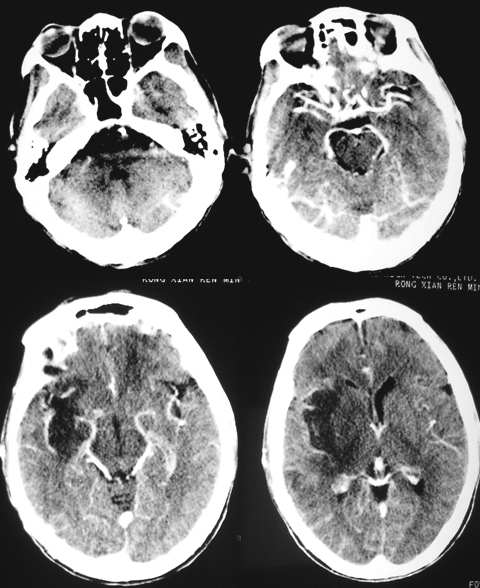

5mm;

支持左恻基底节区脑腔梗伴脑水肿;

右侧侧裂池与左侧大致对称、无明显扩大。

右侧侧裂池与左侧大致对称、无明显扩大。问题应该不大的

不就是---------脑梗塞吗!!!病侧侧裂因脑水肿变窄。

ct增强未见低密度灶强化,应该是右侧基底节区脑梗塞并脑水肿。

明明是脑梗塞,大家却想得很多,不要考虑一些不常见的疾病。

右侧基底节区脑梗塞

右侧基底节区脑梗塞,伴脑水肿